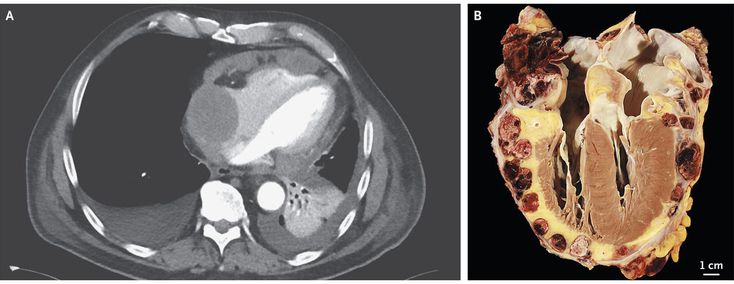

A 66-year-old man presented to the emergency department with a 4-day history of shortness of breath and swelling in the legs. He also reported feeling fatigued and having had a recent 15-kg weight loss. A transthoracic echocardiogram showed a mass in the right atrium that appeared to be infiltrating the pericardium. This mass was also visualized on computed tomography of the chest (Panel A). No evidence of metastatic lesions was found on 18F-fluorodeoxyglucose positron-emission tomography. Examination of a biopsy specimen from the lesion revealed high-grade angiosarcoma. Tumor-debulking surgery was performed, and adjuvant chemotherapy was planned; however, hemodynamic instability developed, and despite receiving maximal supportive therapy, the patient died in the intensive care unit. An autopsy was performed, and gross pathological examination of the heart revealed extensive infiltration of the tumor into the epicardium (Panel B).